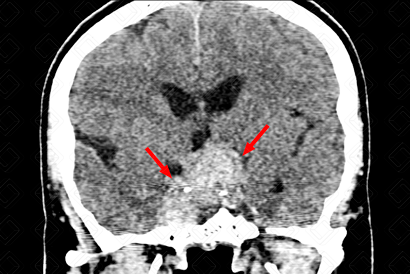

Descrição das figuras: Tomografia computadorizada do crânio pós-contraste evidenciando lesão intrasselar, com extensão suprasselar (formato em 8), com ávida captação pelo meio de contraste, envolvendo os seios cavernosos, de forma mais evidente à direita (setas vermelhas).

Macroadenoma hipofisário: Grupo de lesões pertencentes aos adenomas hipofisários, sendo neoplasias caracteristicamente com seu surgimento intrasselar. Os adenomas hipofisários dividem-se em: microadenomas (lesões com 10 mm ou menos) e macroadenomas (lesões superiores a 10 mm, apresentando na maioria dos casos componente suprasselar). [cms-watermark]

O adenoma hipofisário com extensão suprasselar (ou macroadenoma) tem aspecto de uma "figura de 8" ou boneco de neve, pois é suavemente comprimido ao nível do diafragma selar. Corresponde a cerca de 33-55% das massas suprasselares nos adultos.

Aspectos de imagem: Como já dito acima, são lesões intra e suprasselares, com aspecto em 8 ou boneco de neve e que realçam fortemente e de forma heterogênea pelo meio de contraste. As calcificações são raras. Na ressonância magnética, o sinal da lesão é variável, mas, na maioria dos casos, seu sinal é semelhante à substância cinzenta nas sequências (figuras acima). Pode existir presença de nível líquido nas apoplexias.

Pode ser muito agressivo com erosão do assoalho selar, invasão do seio cavernoso e envolvimento da carótida interna.